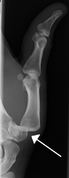

Hand and finger dislocations

- Finger dislocations

- Thumb dislocations

- Hand dislocations